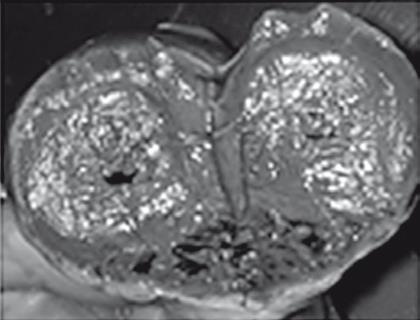

Иллюстрация к книге — Неалкогольная жировая болезнь печени [i_043.jpg]

Индуративный панкреатит

Рис. 38. Летальный случай пациентки с острым отравлением алкоголем